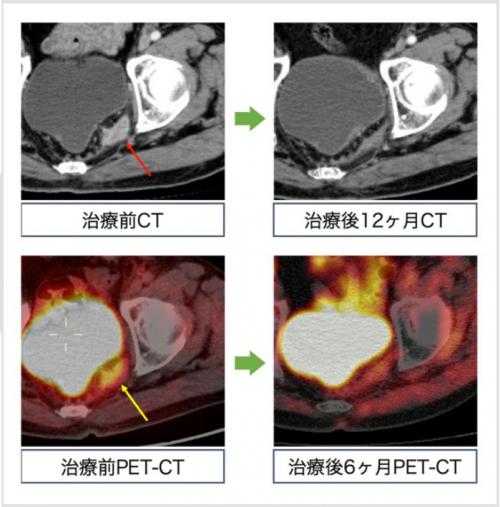

🔵症例の紹介

大腸がん術後の骨盤内局所再発(赤↓)に対して重粒子線治療73.6Gy/16回を行いました。PET画像では治療前には腫瘍に一致して高いFDGの集積(黄↓)を認めましたが、治療後にはFDGの著明な集積低下を認めました。

図 症例の紹介